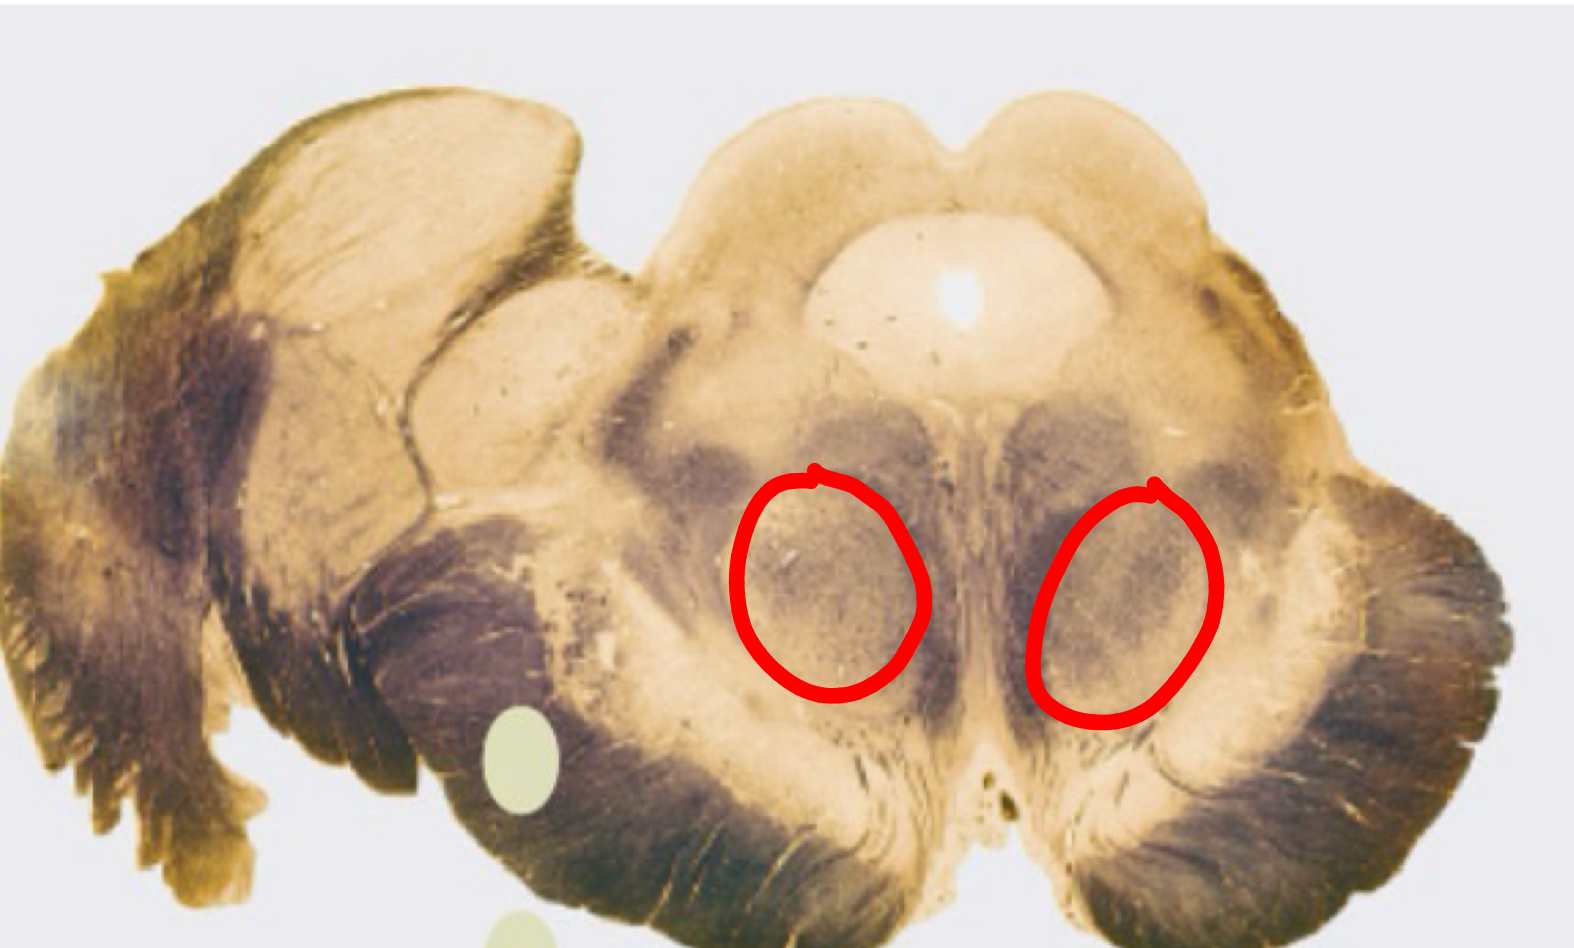

interposed nucleus (globose + emboliform)

dentate nucleus